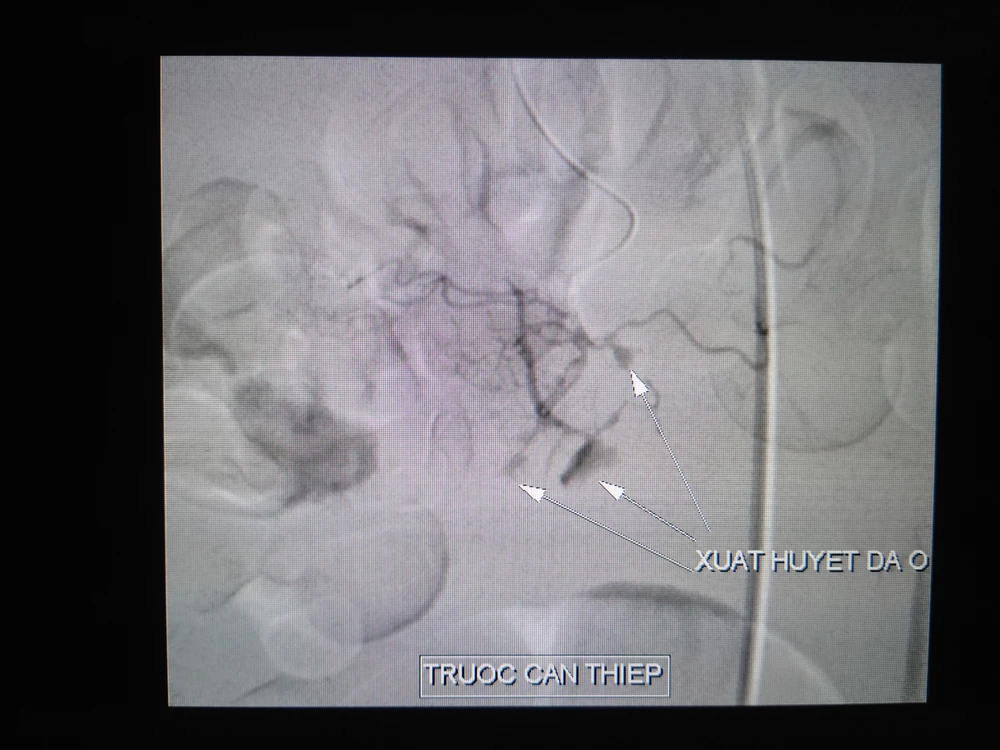

Động mạch vị tá tràng trước và khi can thiệp. Ảnh: BVCC 1 Động mạch vị tá tràng trước và khi can thiệp. Ảnh: BVCC 2

Động mạch vị tá tràng trước và khi can thiệp. Ảnh: BVCC

Kết quả chụp và can thiệp nội mạch xác định bệnh nhân bị xuất huyết nội do vỡ phình động mạch vị tá tràng, nhiều ổ thoát mạch từ nhánh của động mạch vị tá tràng cấp máu vùng tá tràng đoạn DIII, tắc hoàn toàn nhánh thoát mạch.